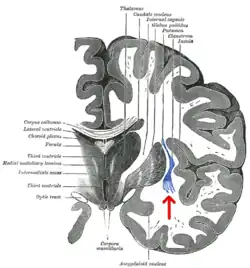

Transverse section of human cerebrum. The claustrum is indicated by the arrow. | |